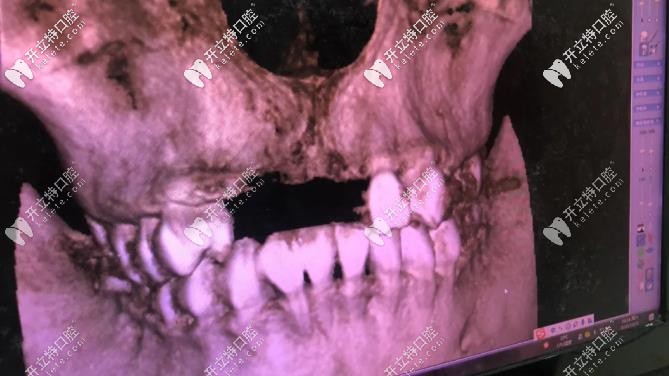

▼這個全景影像檢查可快,幾分鐘就出來▼

全景影像檢查可快,幾分鐘就出來

由于我長期帶假牙,牙骨頭薄,后期種牙手術(shù)難度較大;唯美口腔:彭參醫(yī)師在牙齒缺失修復(fù)、復(fù)雜種植這方面很擅長,就找的他,(我家人目標(biāo)很明確的,對癥下藥)。

1年多點完成種植,之前缺牙時間長,再加上長期戴假牙,彭醫(yī)生:說我的骨頭比較?。ㄕ7N牙厚度:6.5-7毫米,我骨厚度就:3毫米),所以要增量骨組織;我是四顆門牙缺失,種2顆植體,然后戴四連冠就好;現(xiàn)在明白,做種植牙,并不是缺幾顆種植牙幾顆。